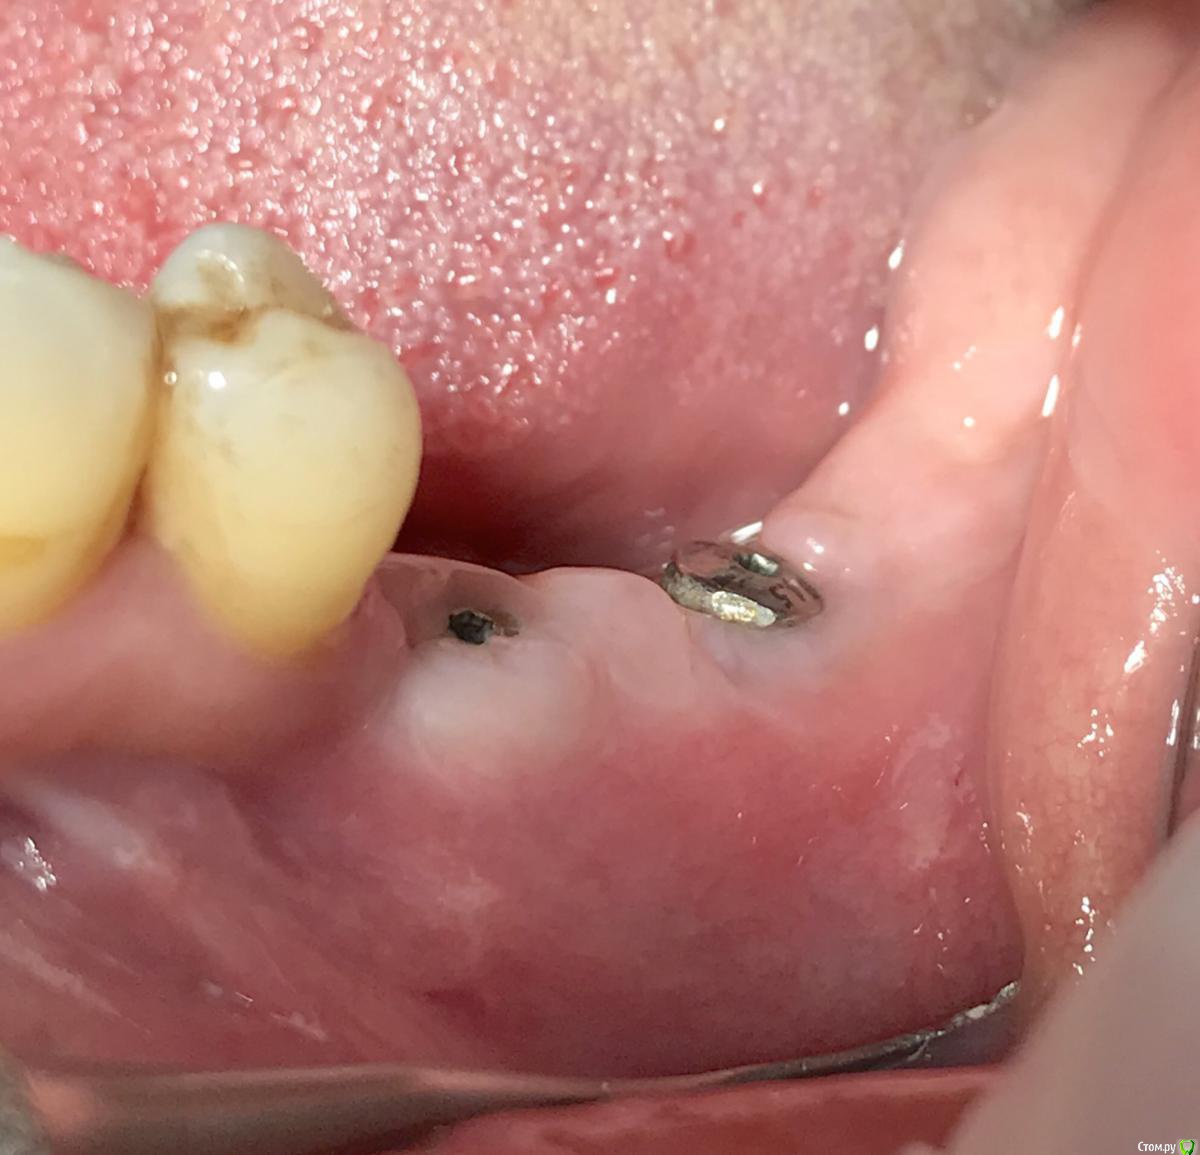

колесников Опубликовано 6 марта, 2019 Автор Поделиться Опубликовано 6 марта, 2019 Продолжение. За прошедшее время произведён асл,замена формирователей на 6ки. Периотест (-6) Ссылка на комментарий

колесников Опубликовано 13 марта, 2019 Автор Поделиться Опубликовано 13 марта, 2019 Ну чтож, прошло 3 месяца,самое время посмотреть что там на кт. 1 Ссылка на комментарий